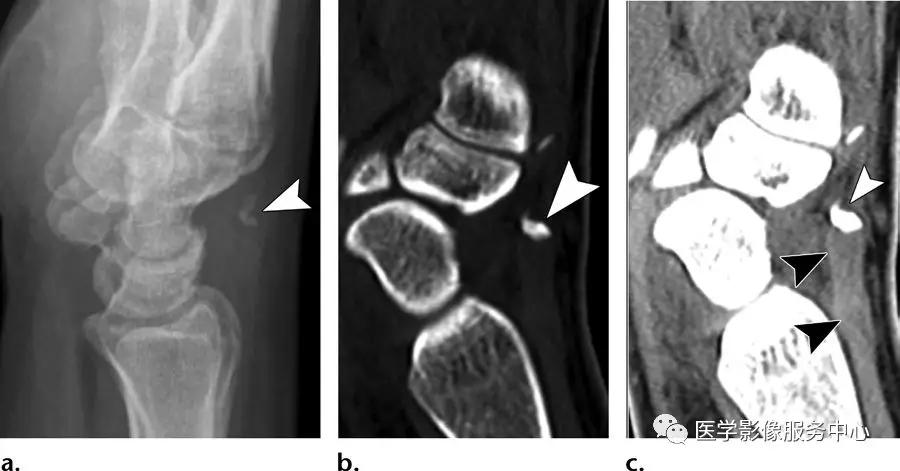

桡侧腕长伸肌撕脱:

(左)背侧撕脱骨片影。(中,右)撕脱骨片影(白色箭头)连接于桡侧腕长伸肌腱(右图中的黑色箭头),导致骨碎片向近端移位。